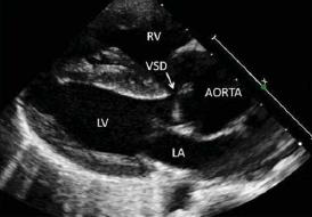

Com base na patologia ilustrada a seguir, qual defeito associado é mais comumente encontrado?